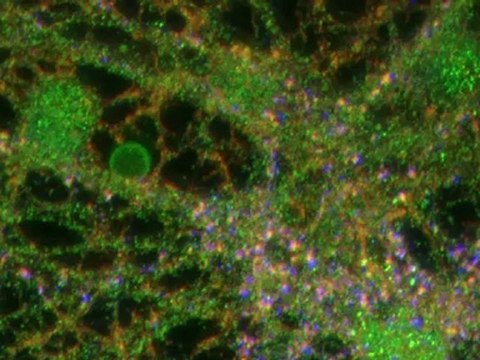

LAS NEURONAS

NEURONAS